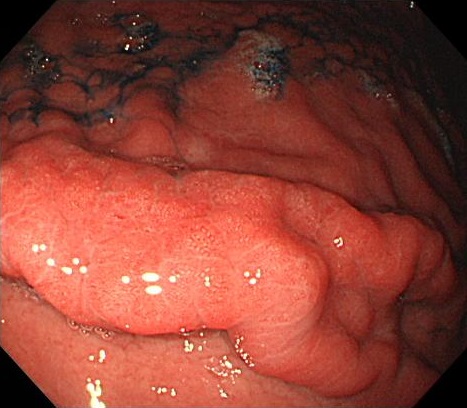

5. 皺壁腫大、蛇行

胃体部のひだが通常より太いく蛇行した状態をいいます。胃レントゲン検査で指摘されることが多いのが特徴です。